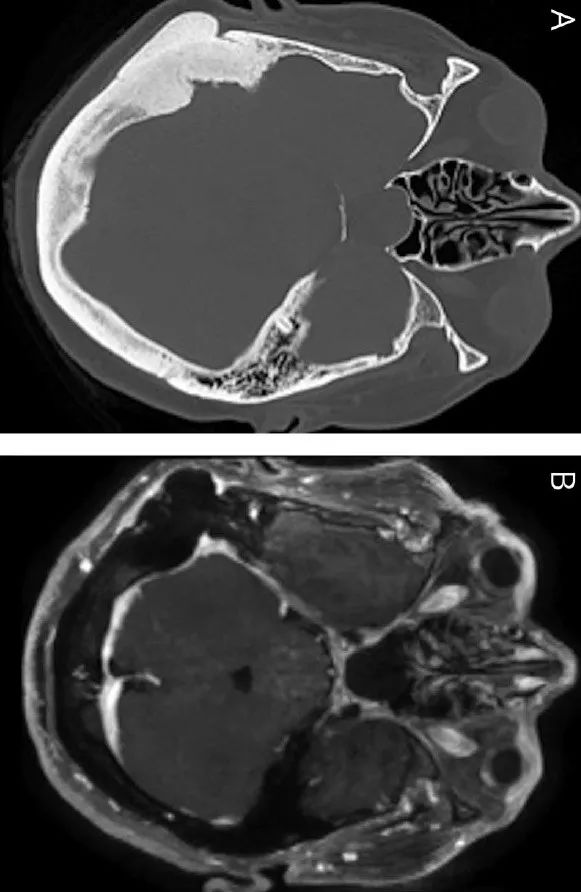

头 mri 显示空蝶鞍(下图 1a),双侧视神经萎缩(下图1b),乳突骨瘤